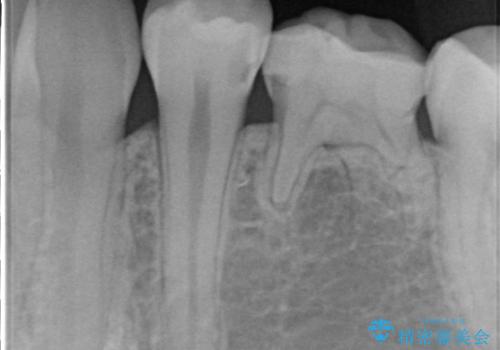

- 定期検診にてむし歯を認めたため、セラミックインレーにて修復を行いました。

e-max プレスインレーにて修復治療を行っているため適合性及び審美性の高い治療を行うことができます